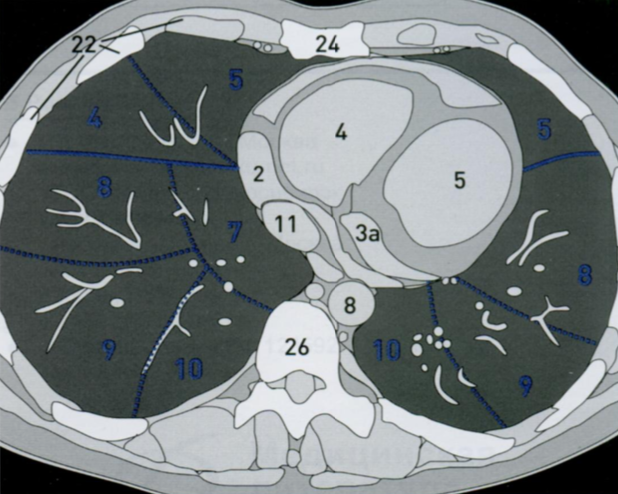

КТ грудной клетки №4

Назовите все анатомические структуры, которые Вы знаете, на данном КТ срезе (11).

Найдите грудные позвонки и грудину. Затем верхнюю полую вену, ушко правого предсердия, восходящую и нисходящую аорту, легочный ствол, левое предсердие и легочные сосуды, непарную вену и пищевод.

A

26 - грудные позвонки

24 - грудина

1 - верхняя полая вена

2а - ушко правого предсердия

7 - восходящая аорта

9 - легочный ствол

3 - левое предсердие

10 - сосуды легких

8 - нисходящая аорта

15 - непарная вена

16 - пищевод

Синим цветом отмечены номера сегментов.